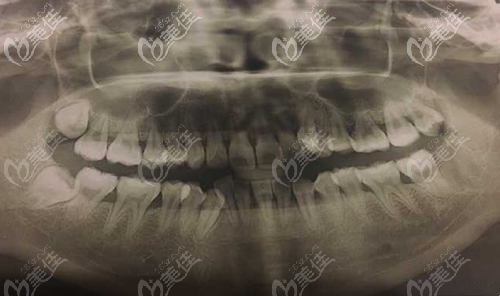

當(dāng)正畸醫(yī)生宣布你需要拔掉多顆正畸牙后,才能做矯正,此時(shí),是不是好擔(dān)心拔牙矯正會不會出現(xiàn)什么后遺癥?來看看真相是怎樣的....... b1606 G0 V0